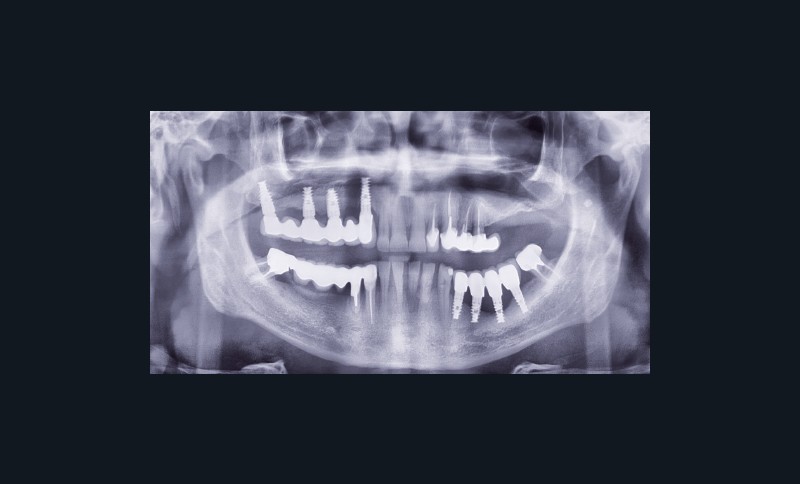

Question 1. Le carcinome épidermoïde, l’épulis et le granulome pyogénique peuvent a priori être évoqués tous les trois. La petite taille et le siège classiquement labial de l’hyperplasie endothéliale intravasculaire [4] permettent d’écarter ce diagnostic. Dans tous les cas, seul l’examen anatomopathologique permet d’étiqueter la lésion.

Le carcinome épidermoïde doit être évoqué du fait des caractéristiques de la lésion, de l’adénopathie sous-mandibulaire et du passé tabagique du patient.

L’épulis inflammatoire, pseudotumeur inflammatoire chronique, se développe généralement sur la gencive marginale ou sur une papille interdentaire. La lésion est habituellement sessile et mesure en moyenne 5 à 10 mm de diamètre. Il est indolore, érythémateux et rarement ulcéré. L’origine traumatique de l’épulis peut correspondre au cas présenté (espaces papillaires insuffisants).

Le granulome pyogénique (syn. botryomycome, hémangiome capillaire lobulé) est une lésion bénigne d’origine vasculaire [2]. Il siège sur la peau et, surtout, sur les muqueuses, en particulier les lèvres, les gencives, les joues et la langue. La lésion en bouche peut être unique ou multiple. Elle se présente comme un nodule saillant, souvent sessile, rarement pédiculé. La lésion est…